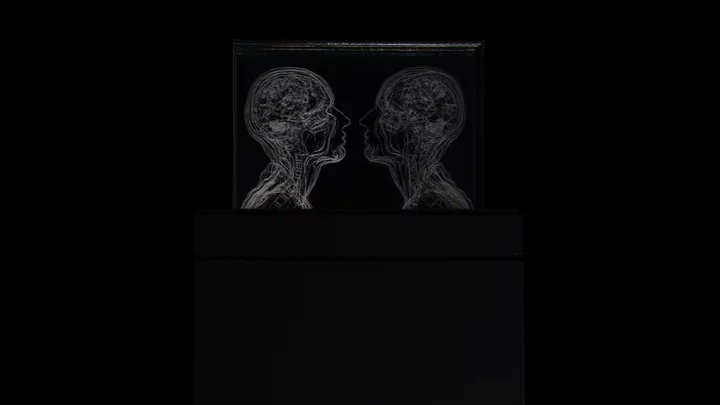

Self-portraits

Angela Palmer developed a technique to reconstruct anatomical forms, both of human and animal subjects: she draws or engraves details from MRI or CT scans on to multiple sheets of glass, layer by layer, to create three-dimensional sculptural drawings 'floating in space'.

She was inspired to adopt this technique after seeing a laboratory model by the Nobel winning scientist Dorothy Hodgkin, which is in the History of Science Museum in Oxford. Hodgkin's model, which was made in the 1940s, represents the penicillin molecule as a three-dimensional form, drawn in a thick black pen on layers of acrylic, held together by bolts. Palmer said: 'I presented the sheets on a vertical rather than horizontal plane, and took details from CT slices through the human head. This method allowed me to expose the extraordinary inner architecture concealed beneath the surface of the human form, thus creating the most objective form of portraiture. The image floats ethereally in its glass chamber, but can only be viewed from certain angles; from above and the side it vanishes and the viewer suddenly finds himself staring into a void.'